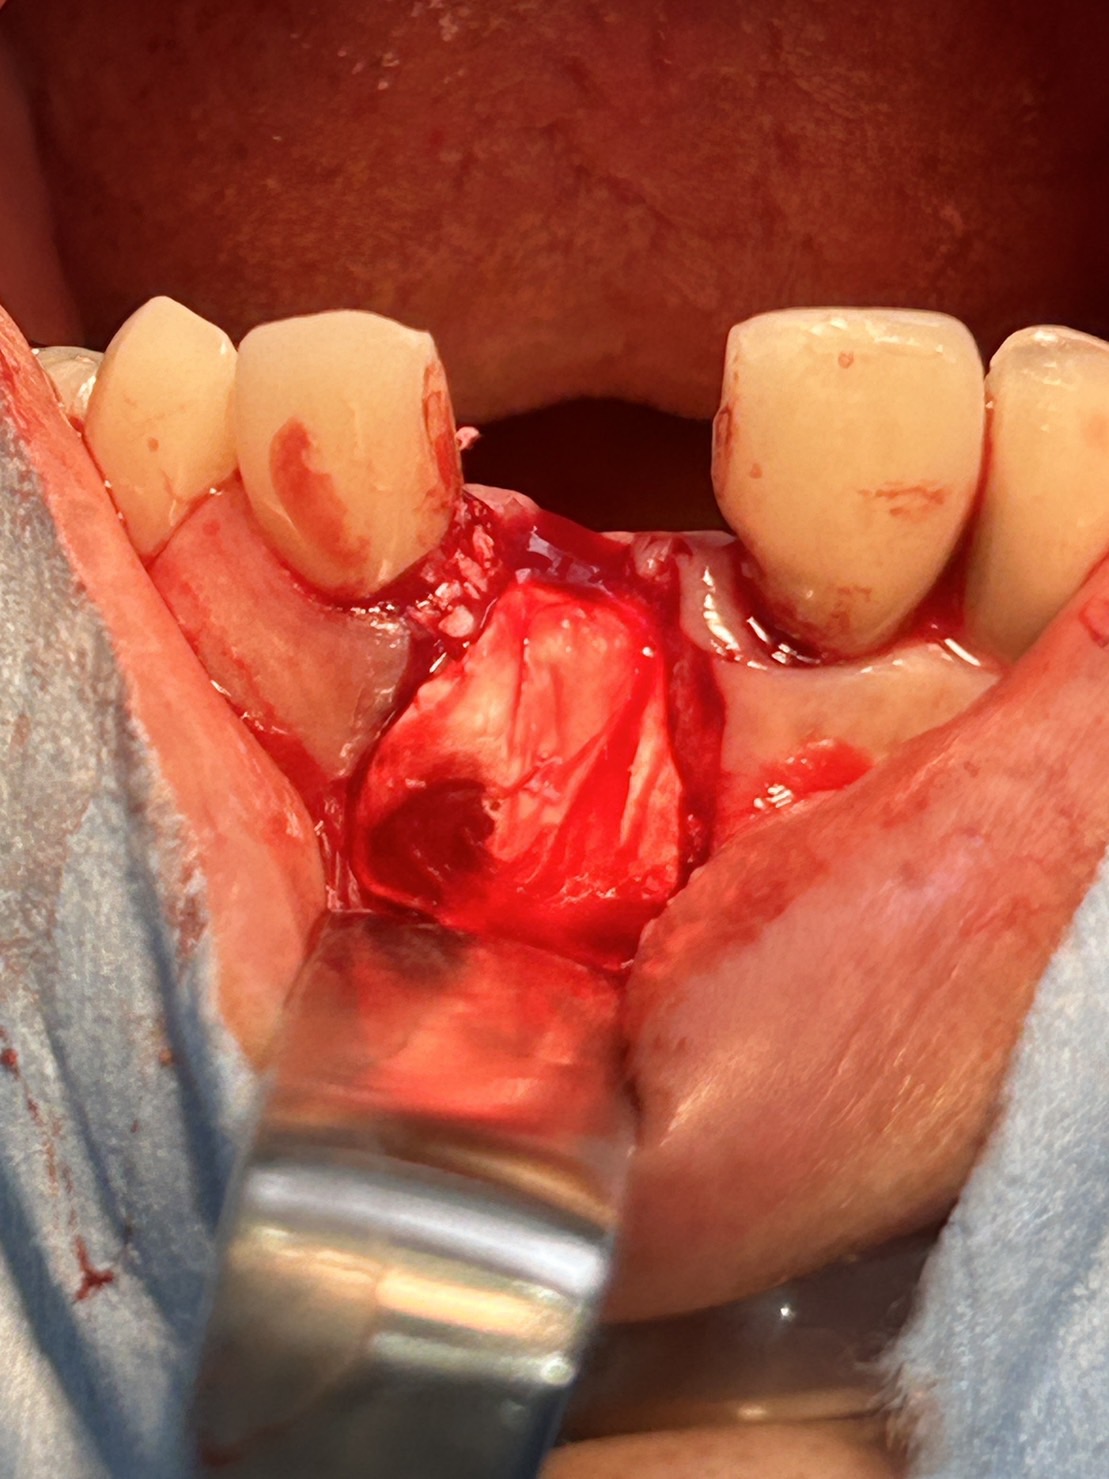

⻭⾁剥離掻爬

⿐⼝蓋神経を搔爬

過剰⻭を取り除く

デコルチケーション